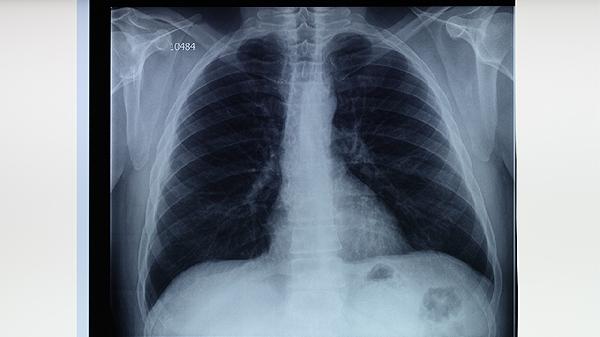

3、肺结核的诊断需要结合影像学检查和实验室检测,如胸部X光片和痰涂片检查。普通咳嗽的诊断则主要通过病史和体格检查,必要时进行血常规或过敏原检测。